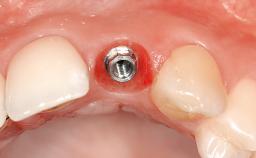

Bruno Schmid graduated as a dentist from the University of Bern in 1989. He worked several years in private practice and then continued his postgraduate studies in the Department of Periodontology and Fixed Prosthodontics at the University of Bern. In 1996 he was certified as a periodontist (SSO).

Since 1997 he has a private practice in Belp Switzerland and still works part-time at the University of Geneva. He is an ITI Fellow and the current Chair of the Swiss ITI Section as well the vice president of the Swiss Society of Implantology (SGI). He has presented many clinical programs throughout Europe and Asia.